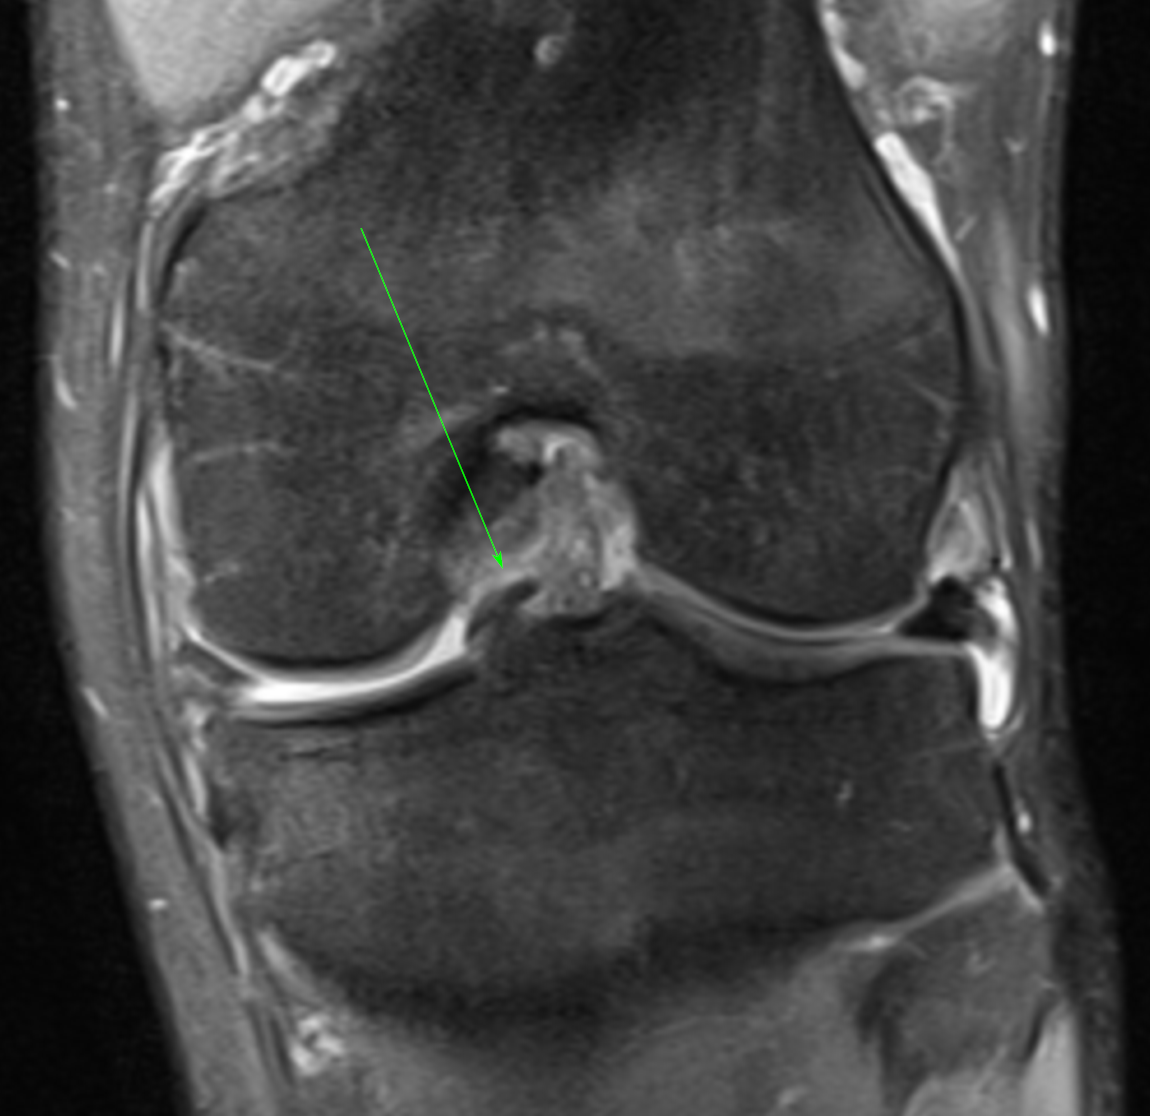

21 y, male. Intermittent locking and ongoing medial compartment pain followingtwisting injury.

PD FS Cor & Axi: Vertical longitudinal meniscal tear with mesial displacement of free edge fragment into intercondylar notch (arrow). Displaced fragment maintains anterior and posterior attachments to peripheral remnant (anterior attachement can be seen on axial image).